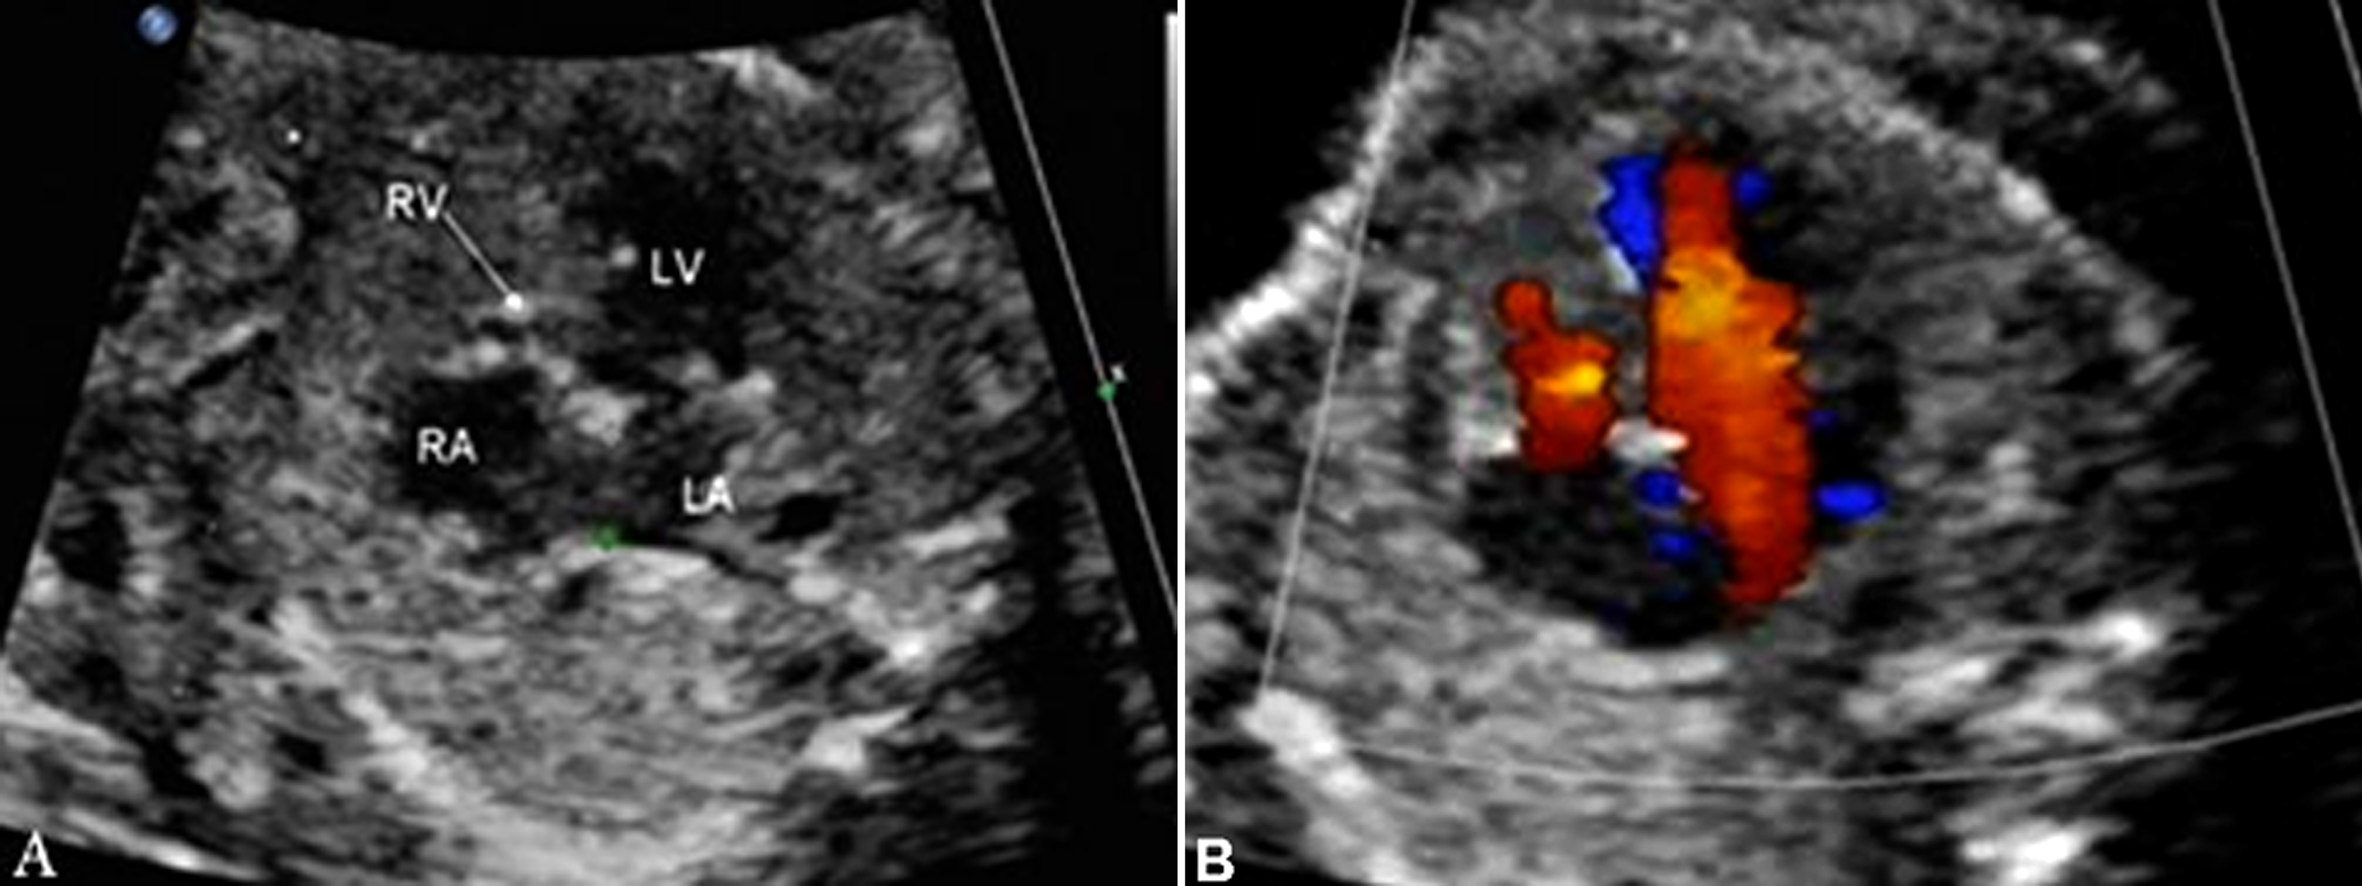

2. 超声诊断要点 二维超声显示左、右心室不对称,绝大多数右心室明显小于左心室(图3),少数也可正常大小或明显大于左心室;彩色多普勒超声检查三血管气管切面动脉导管与主动脉弓血流方向不一致,动脉导管内呈逆向血流(图4)。

图3 胎儿右心发育不良:左右心室不对称,RV<LV